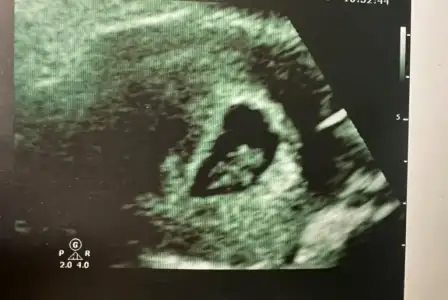

10 haftalık göbeğim ve karından 8 haftalık ultrason görüntüm bu şekilde . Cinsiyet tahmininiz var mı hanımlar 🌸